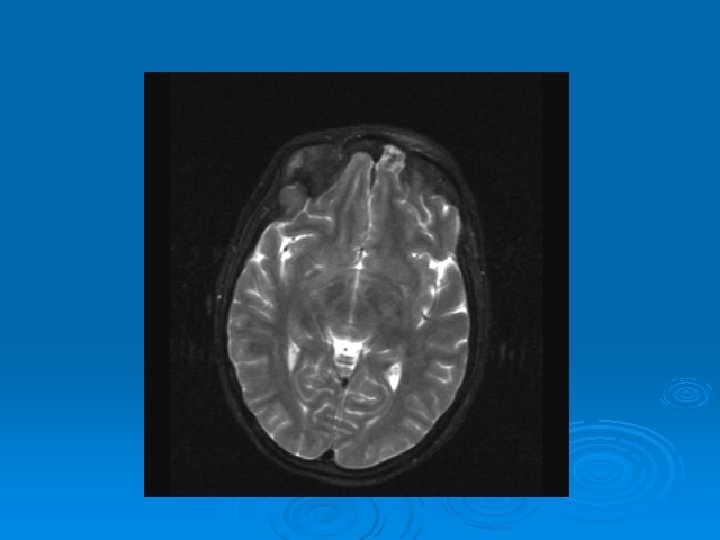

MRI: 2/9/2007 Ø 1. Leptomeningeal enhancement, most prominently seen over the posterior parietal and occipital lobes.

CMV: Ventriculoencephalitis Ø Clinical: Can have abrupt presentation of confusion, apathy, impaired memory, withdrawal, nystagmus, motor weakness, cranial nerve deficits, ataxia, seizures, coma. Can rapidly progress. Ø Labs: CSF: Monocytic Pleocytosis, Low Glucose CMV PCR Positive in CSF: (Sensitivity, Specifity 80, 90%, PPV, NPV, 86 -92, 9598%) Serum CMV viremia Ø Ø Ø MRI: Subependymal enhancement, diffuse hyperintense T 2 WI, ventriculomegaly.

MRI of CMV patient Magnetic resonance images of a patient with cytomegalovirus ventriculitis Ependymal enhancement after injection of gadolinium. DPTA seen on coronal T 1 -weighted image. Ø Highly abnormal ependmal signal on proton densityweighted image of the brain in axial section. Ø Ø See images in: l Arribas et al, Cytomegalovirus Encephalitis, Annals of Internal Medicine, 1996, Vol 125, Issue 7